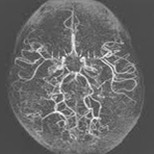

모야모야병은 뇌기저부의 주요 혈관이 서서히 협착되고 막히면서 뇌혈류가 감소하는 만성 진행성 뇌혈관 질환입니다. 협착이 진행된 부위를 대신해 뇌는 생존을 위해 얇고 약한 혈관망을 만들어 혈류를 보충하려 하고, 이 새로운 혈관들이 촬영 영상에서 연기처럼 퍼져 보인다고 하여 ‘모야모야’라는 이름이 붙었습니다. 기전적으로는 내경동맥 말단부와 중대뇌동맥·전대뇌동맥의 기시부에 병변이 가장 잘 생기며, 시간이 지남에 따라 양쪽에 대칭적으로 나타나는 특징을 보였습니다. 이 질환은 단순한 혈관 협착이 아니라 진행성 변화이기 때문에 치료하지 않으면 혈류 부족이 심해지고 뇌 손상이 누적될 수 있습니다. 또한 뇌기능이 체력·호흡·체온 변화 등에 민감하게 반응하기 때문에 과호흡, 울음, 격렬한 운동, 감염 등으로 증상이 악화될 수 있습니다. 즉, 모야모야병은 시간이 지나면서 뇌혈류를 감소시키고 뇌졸중 위험을 높이는 질환이며, 평생 관리가 필요한 만성적 특성을 갖고 있습니다.